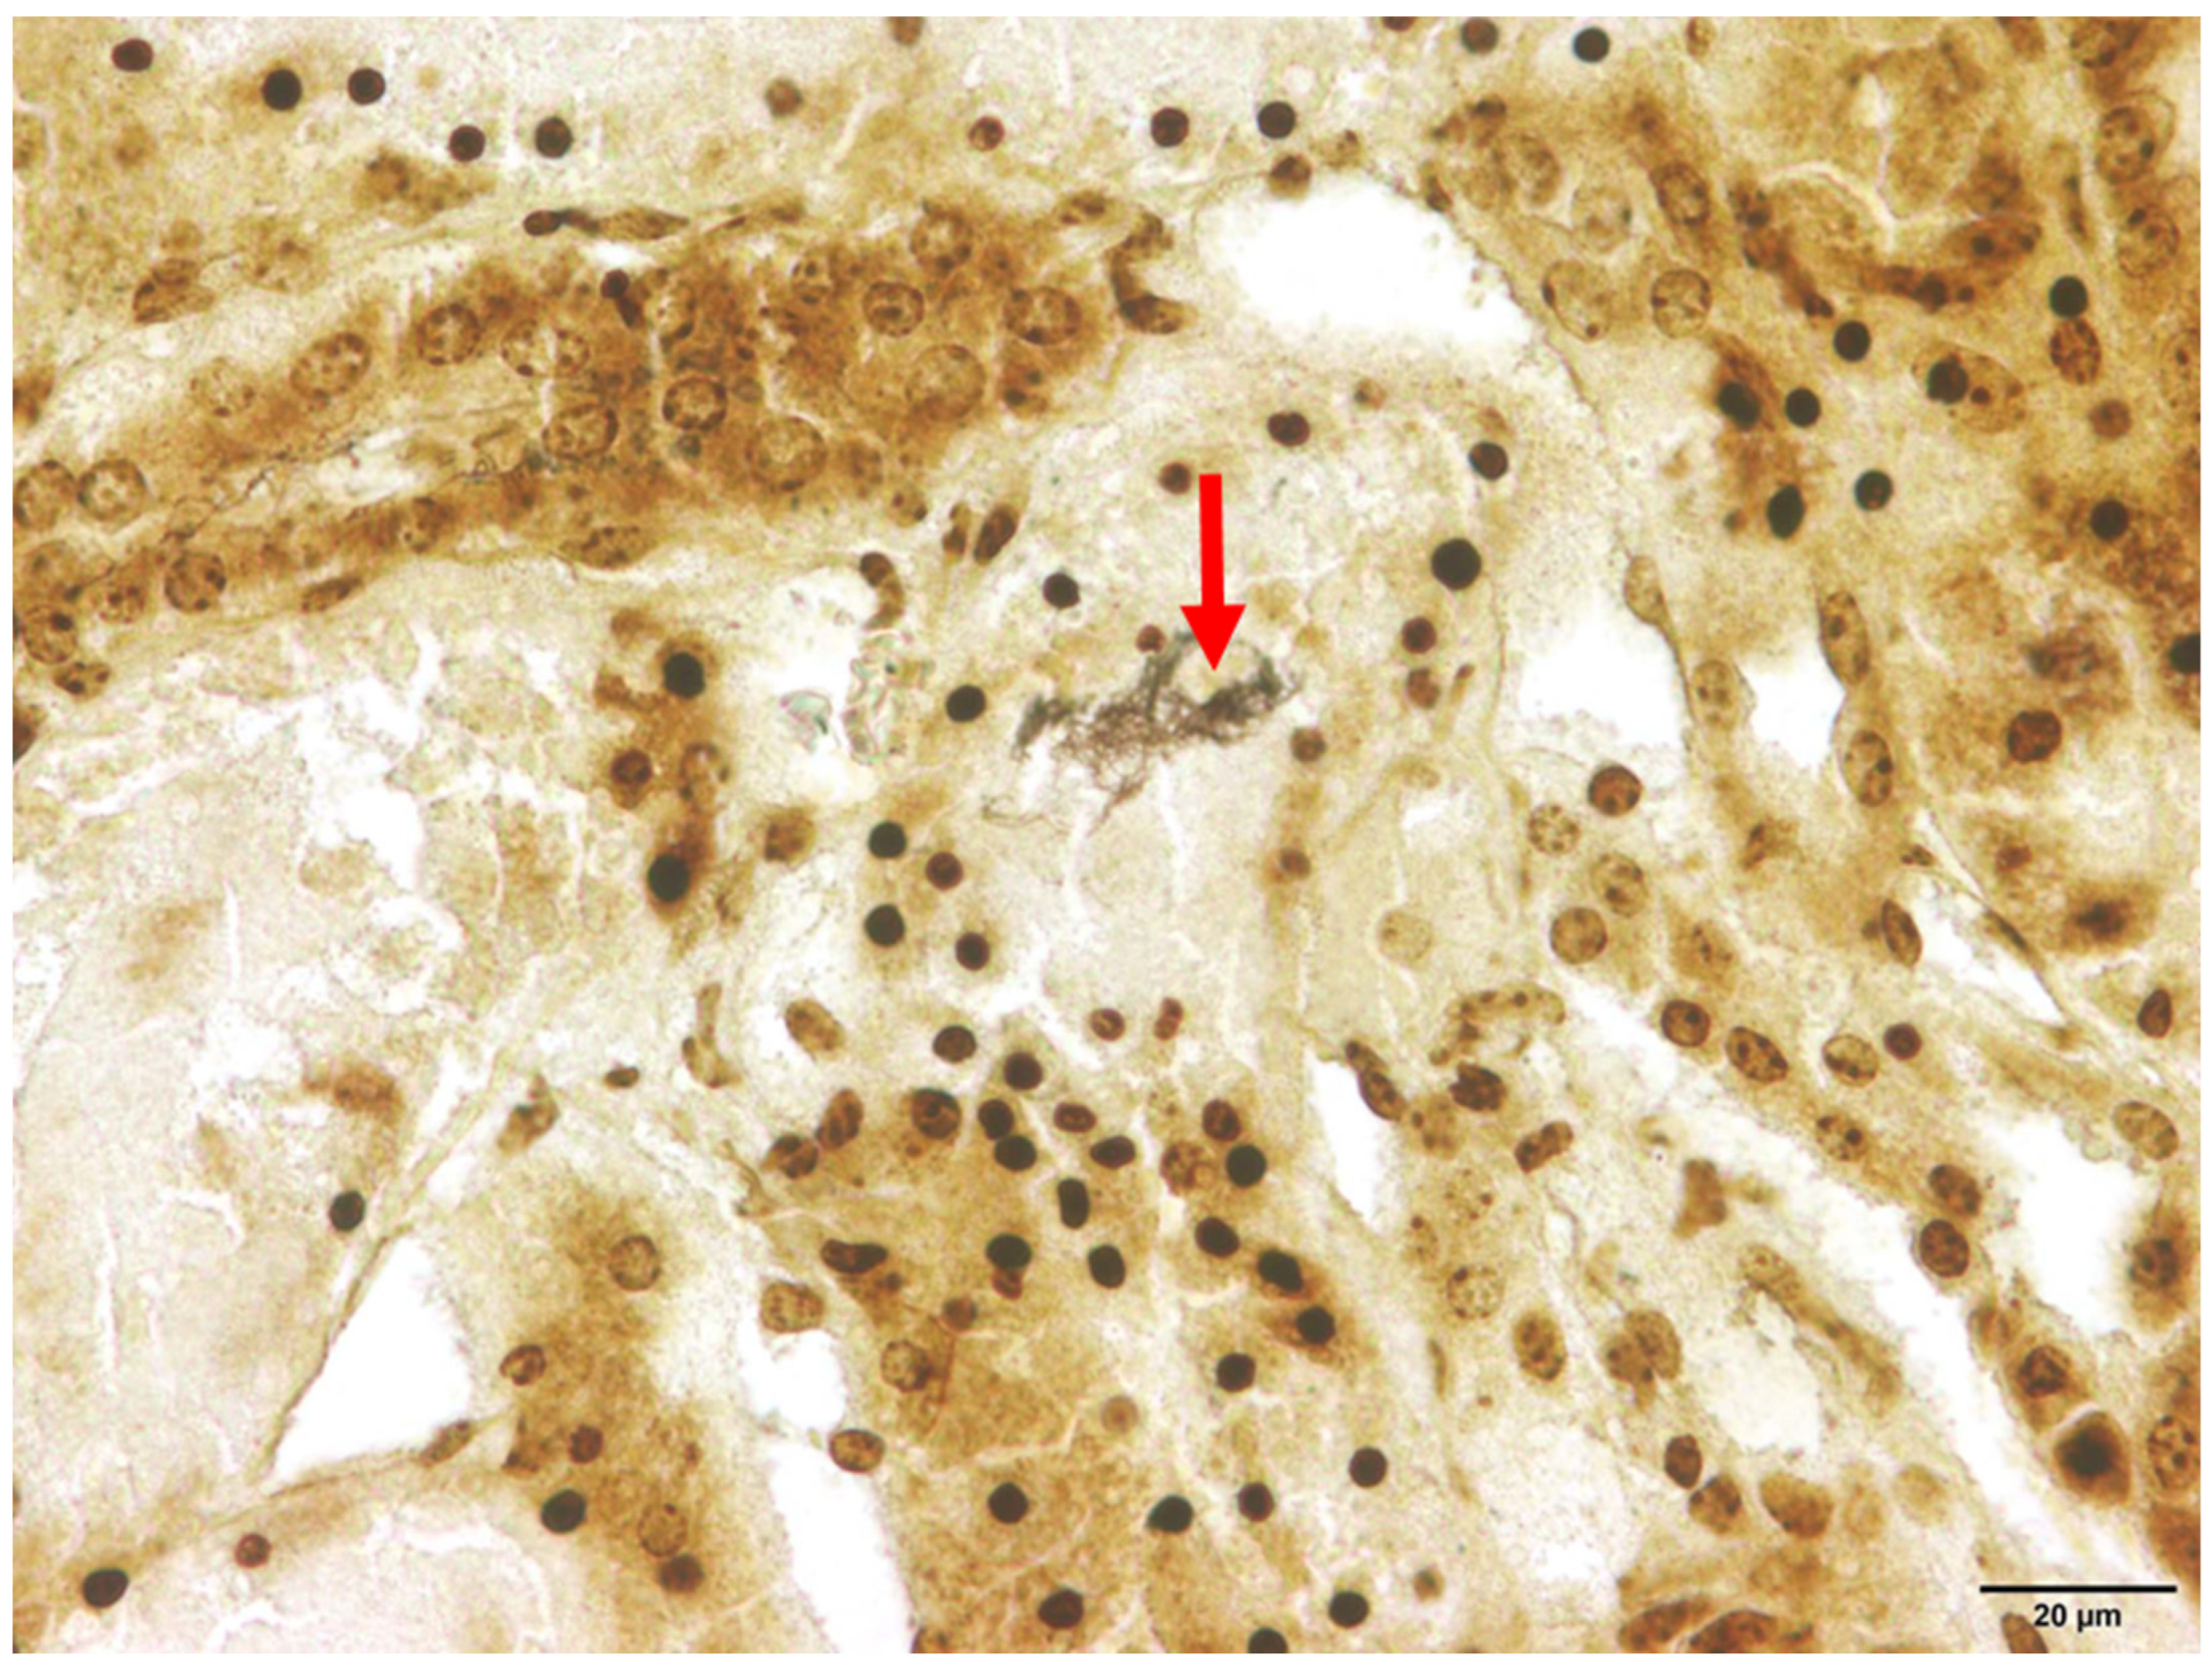

3.3. Histopathology

- Cianciolo, R.; Mohr, F. Urinary system. In Jubb, Kennedy, and Palmer’s Pathology of Domestic Animals, 6th ed.; Maxie, M., Ed.; Elsevier: St. Louis, MO, USA, 2016; Volume 2, pp. 433–439. [Google Scholar]